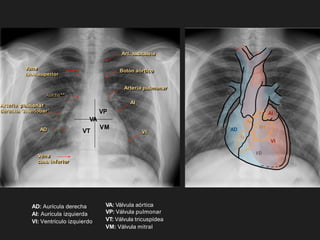

AD: Aurícula derecha AI:Aurícula izquierda VI: Ventrículo izquierdo VA: Válvula aórtica VP: Válvula pulmonar VT: Válvula tricuspídea VM: Válvula mitral AD VD AI VI Tr Mt Ao P Botón aórtico Arteria pulmonar AI VI Art. subclavia Vena cava superior Vena cava inferior Arteria pulmonar derecha ‘interlobar’ AD VA VP VT VM Aorta**